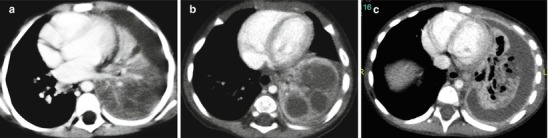

Necrotizing pneumonia or cavitary necrosis is a complication of severe lobar pneumonia, characterized by massive necrosis and liquefaction of lung tissues resulting to multiple cavities rather than a solitary one. It is most commonly caused by S. pneumoniae although Aspergillus and Legionella have also been implicated in the pediatric population (Hodina et al. 2002). Evidence of cavitary necrosis complicating pneumonia is often seen on CT before or in the absence of findings in chest radiography. CT findings include lung consolidation with decreased parenchymal enhancement, loss of lung-pleura margin, and multiple thin-walled cavities lacking an enhancing border. The adjacent visceral pleura is particularly fragile and tends to rupture, causing bronchopleural fistula (Hoffer et al. 1999) (Fig. 13.10). Cavitary necrosis indicates an intense and prolonged illness, but it usually resolves without surgical intervention (Donnelly and Klosterman 1997).

Fig. 13.10.

Necrotizing pneumonia on CT. Left lower lobe consolidation showing diminished perfusion at the posterior region (a). Evolution of lung ischemia with development of multiple fluid-filled cavities (b). Cavitary necrosis of the consolidation with bronchopleural fistula and parapneumonic fluid (c)